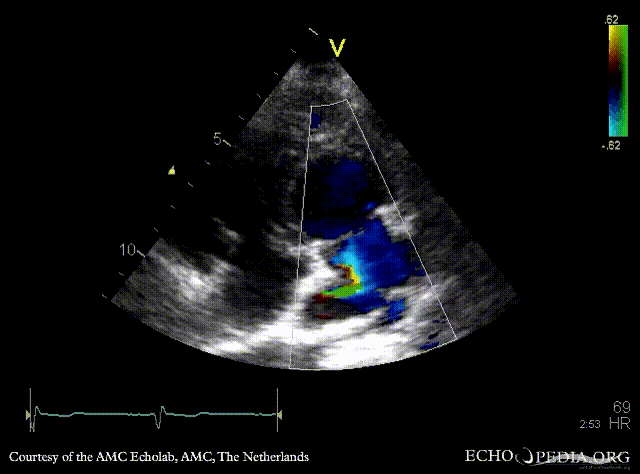

E00582.gif

A4CH with Color Doppler